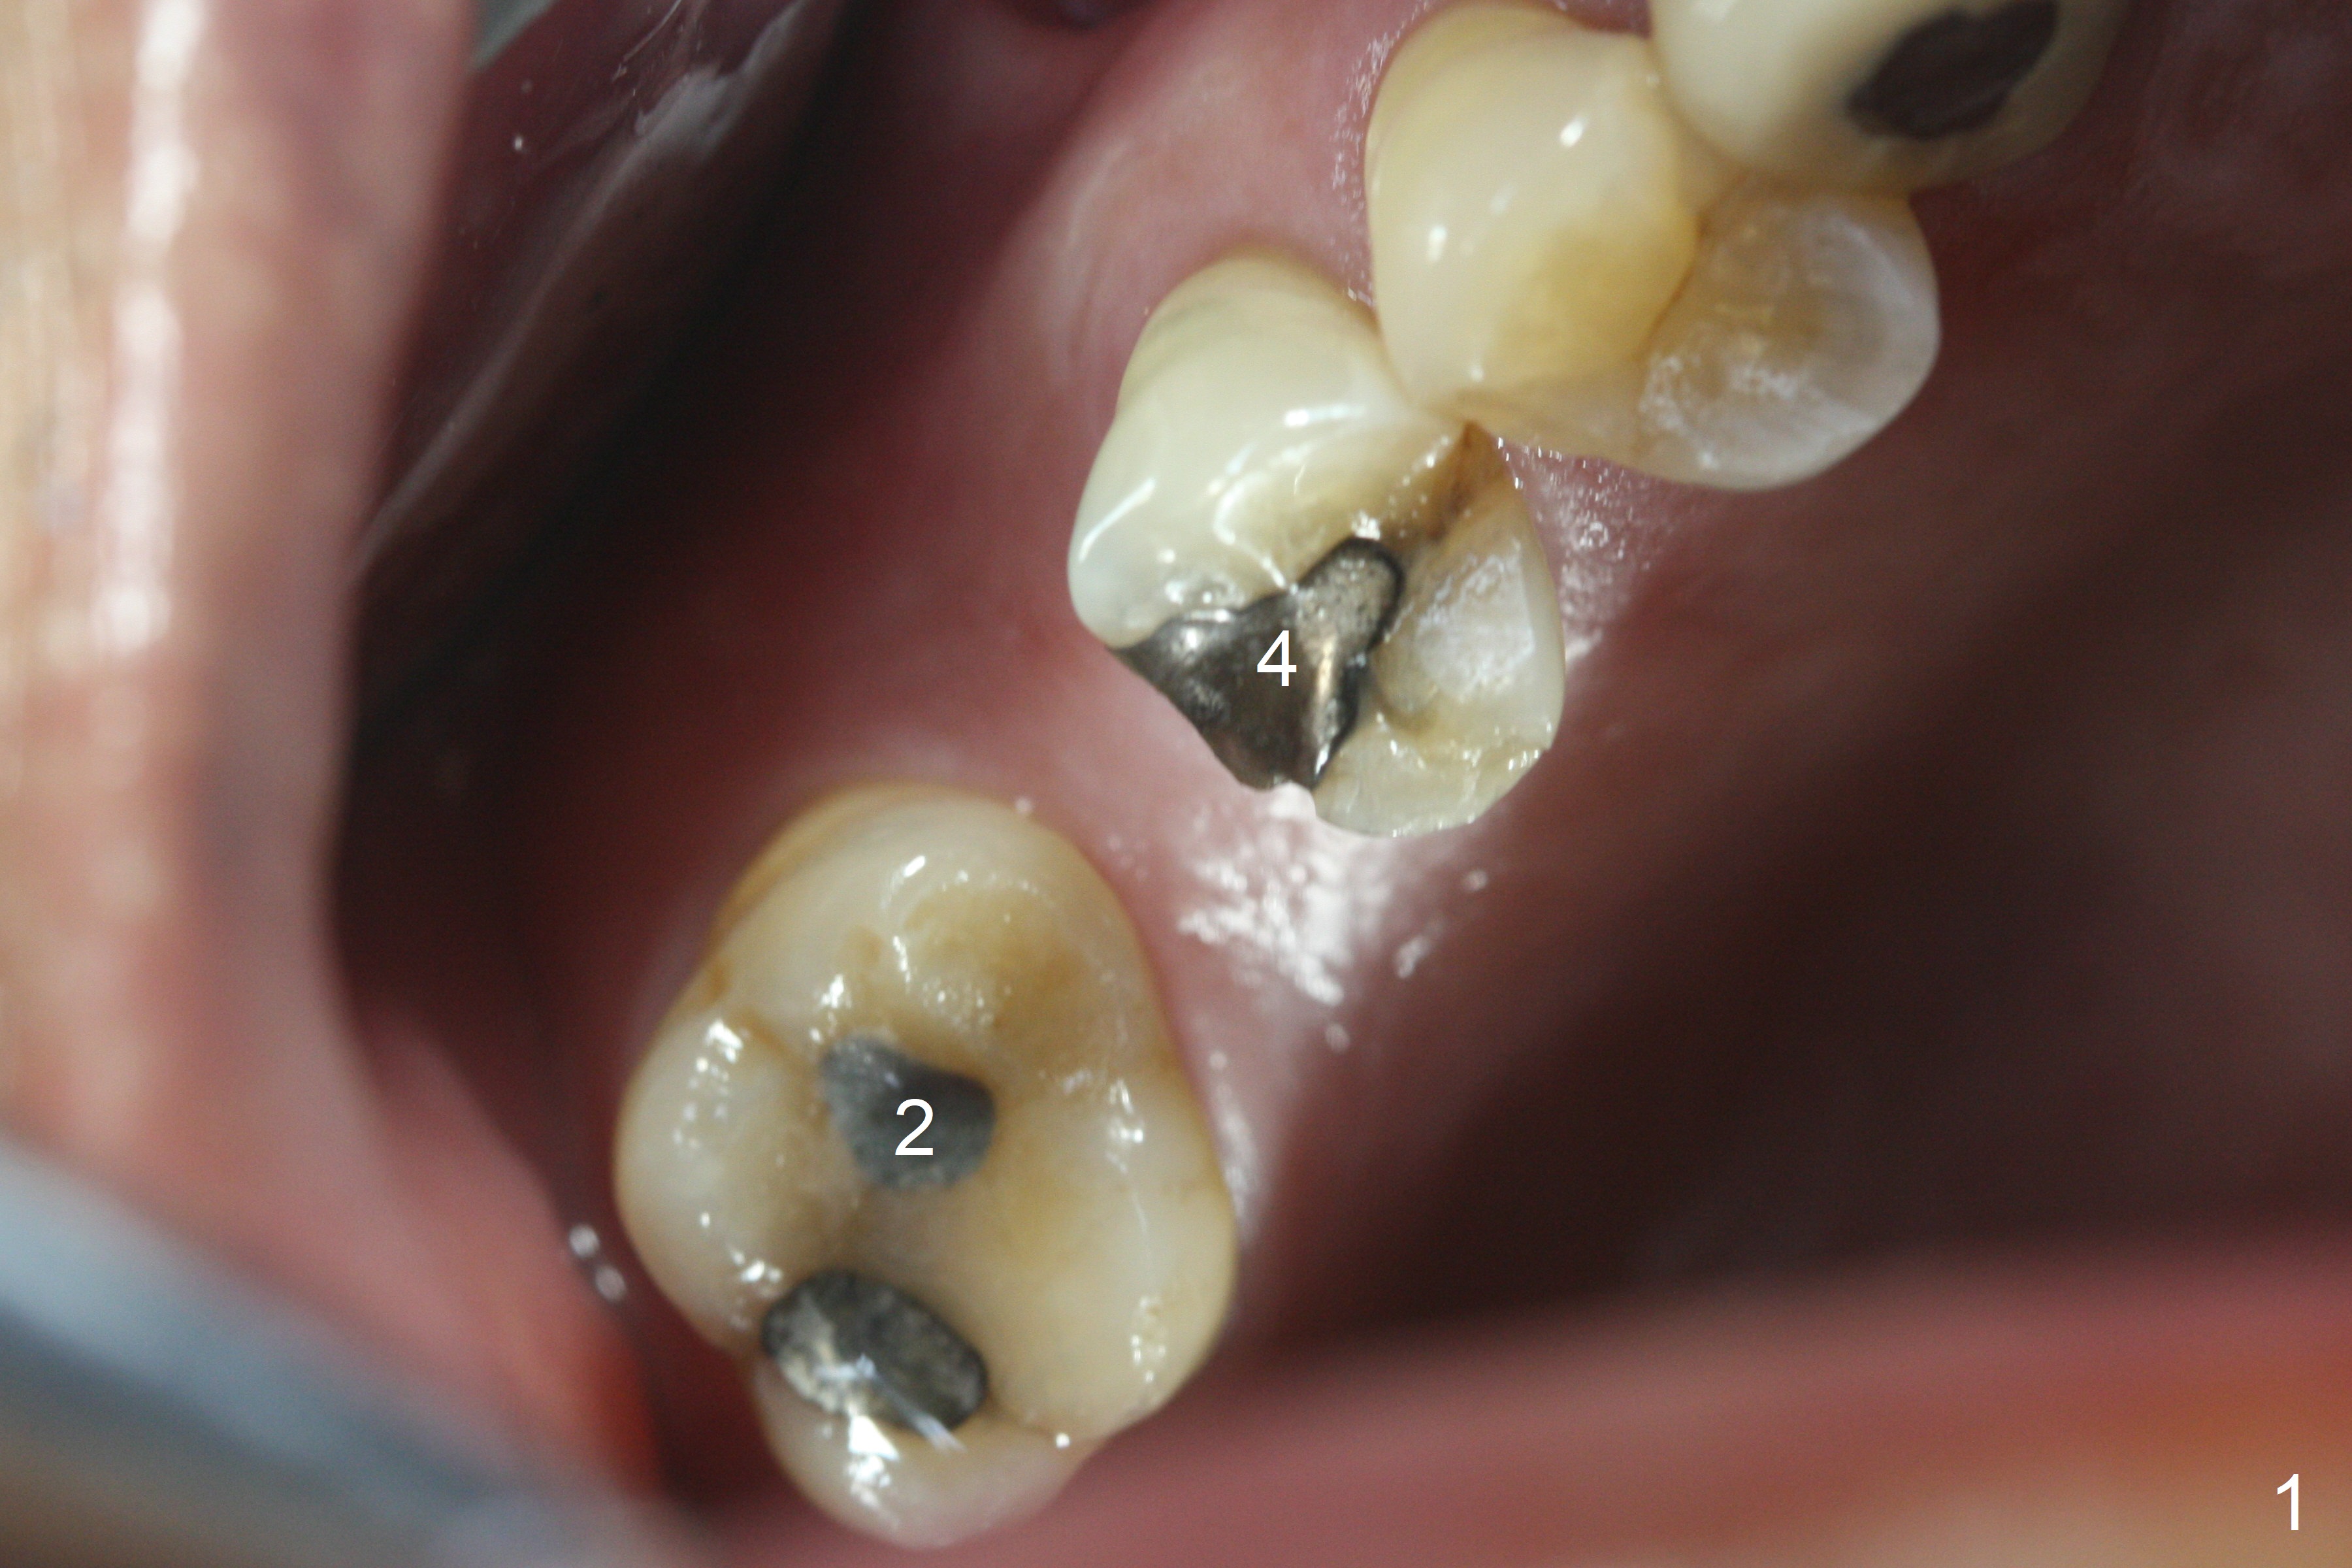

The palatal cusp of the affected 2nd premolar is apparently rotated distal (Fig.1). It is more obvious for the socket (Fig.2): the palatal (P) portion of the socket is more distal than the buccal (B) one. When the gauze is removed (Fig.3), Lindamann bur is used to remove the disto(D)palatal bone of the socket (data not shown), followed by starter drill in the DP wall obliquely (Fig.3'). Once the drill enters the bone for 1-2 mm, the bur is straightened and pushed slightly distal (Fig.3''). Fig.4 shows a parallel pin distal (overcorrect) to the original socket (Fig.4 red dashed line). Sequential osteotomy is conducted until 3.8x13 mm drill for 18 mm (Fig.5): note the 2 steps of the osteotomy (red lines). Since the apical portion of the osteotomy is larger than the drill, a larger implant than expected (5x16 mm) is placed. The implant ends up in the middle of the edentulous area (due to the stepped osteotomy; Fig.6-9; >60 Ncm). Vera allograft is placed (Fig.7-9 *) prior to and after placement of a 6.5x4(3) mm abutment (Fig.8-10). The remaining socket opening is sealed with a piece of Collagen plug (Fig.10 *). The socket is then closed by an immediate provisional (Fig.11 P). The abutment is retightened 2 months postop (Fig.12,13). The crown is cemented 4.5 months postop. Panoramic X-ray and CT are taken nearly 7 months post cementation (Fig.14,15) when the patient is ready for #30 implant guide preparation.